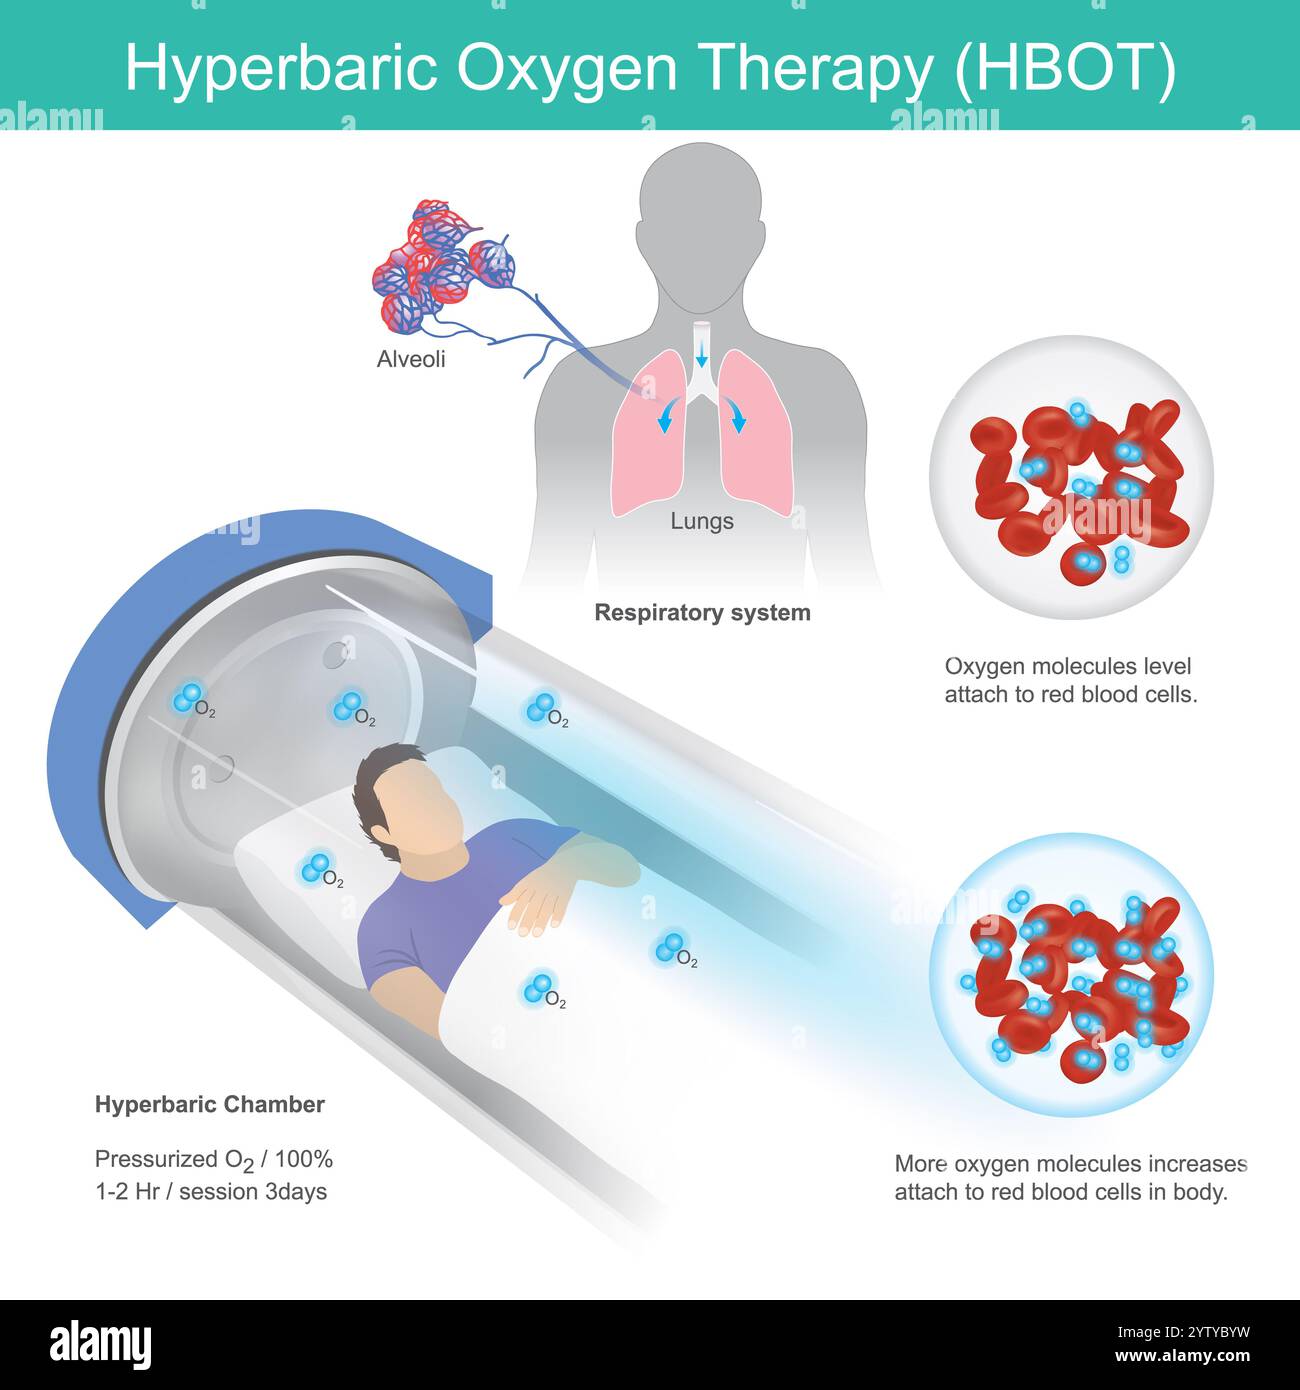

Ventola di ventilazione elettrica. Foto Stockhttps://www.alamy.it/image-license-details/?v=1https://www.alamy.it/ventola-di-ventilazione-elettrica-image634927101.html

Ventola di ventilazione elettrica. Foto Stockhttps://www.alamy.it/image-license-details/?v=1https://www.alamy.it/ventola-di-ventilazione-elettrica-image634927101.htmlRF2YTYBYW–Ventola di ventilazione elettrica.